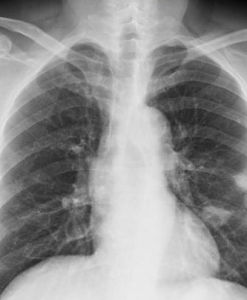

肺部影像二、影像學檢查胸部X線檢查可以發現肺內病變的部位、範圍,有無空洞或空洞大小,洞壁厚薄等。X線對各類結核病變的透過度不同,通過X線檢查大致能估計結核病灶的病理性質,並能早期發現肺結核,以及判斷病情發展及治療效果,有助於決定治療方案。必須指出,不同病因引起的肺內病變,可能呈現相似的X線影像,故亦不能僅憑X線檢查輕易確定肺結核的診斷。

X線攝片結合透視有助於提高診斷的準確性,可發現肋骨、縱隔、膈肌或被心臟遮蓋的細胞病灶,並能觀察心、肺、膈肌的動態。肺結核的X線表現包括:纖維鈣化的硬結病灶,表現為密度較高、邊緣清晰的斑點、條索取或者結節;浸潤性病灶,表現為密度較單,邊緣模糊的雲霧狀陰影;乾酪樣病灶,表現為密度較高,濃淡不一,有環形邊界透光區的空洞等。

肺結核病灶通常在肺上部、單側或雙側,促成時間較長,且有多種不同性質的病灶混合存在及肺內播散跡象。凡X線胸片上顯示滲出性或滲出增殖性病灶、乾酪樣肺炎、乾酪樣病灶、空洞(除淨化空洞外),均提示為活動性病變;增殖性病變、纖維包裹緊密的乾酪硬結灶火及纖維鈣化灶等,均屬非活動性病變。

活動性病灶的痰中仍可找到結核菌。由於肺結核病變多為混合性,在未達到完全增殖或纖維鈣化時,均仍應考慮為活動性。肺部CT檢查對於發現微小或隱蔽性病變,了解病變範圍及肺病變鑑別等方面均有幫助。